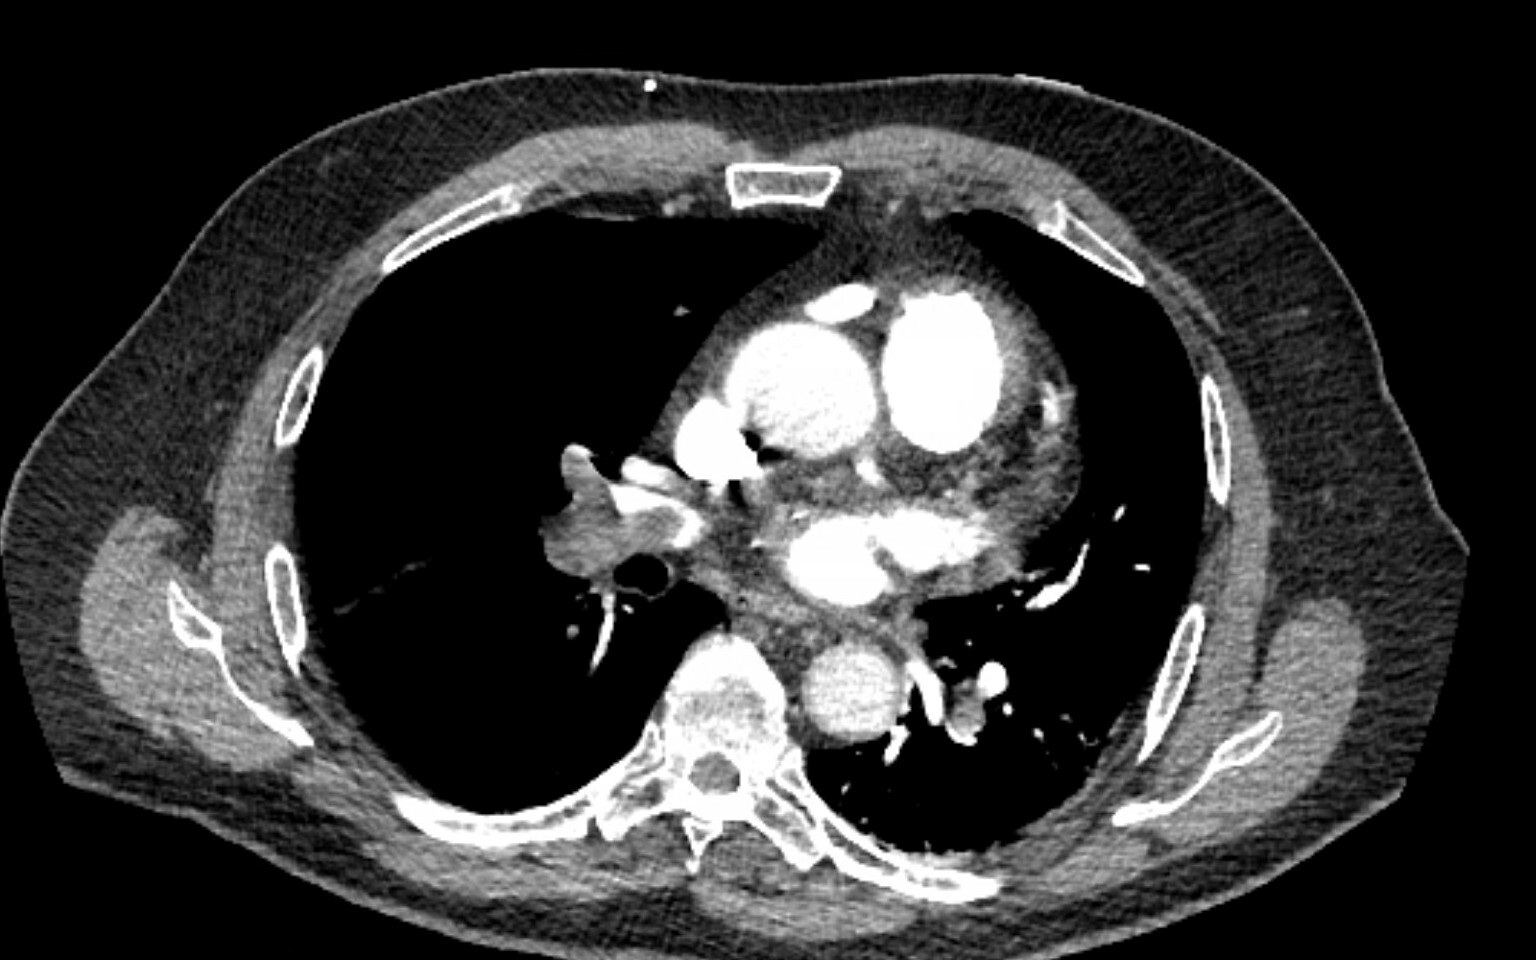

A 61-year-old woman with a history of hyperlipidemia, hypertension, stage 1 chronic kidney disease, and a baseline creatinine level of 1.5 mg/dL (132.6 μmol/L) presented yesterday with acute hypoxic respiratory failure from multilobar pneumonia. She underwent intubation last night, after which she developed mild shock, and she currently is receiving a 0.15 μg/kg/minute norepinephrine infusion. This morning, her ventilator settings have stabilized with assist control volume control with tidal volume of 350 mL, PEEP of 10 cm H₂Ο, and FiΟ₂ of 0.6. Her urine output has decreased, and she has been making only 5 to 10 mL of urine an hour for the last 12 hours. Her laboratory tests are notable for the results shown in Figure 1. Enteral feeding was started this morning at a trophic rate of 10 mL/hour.